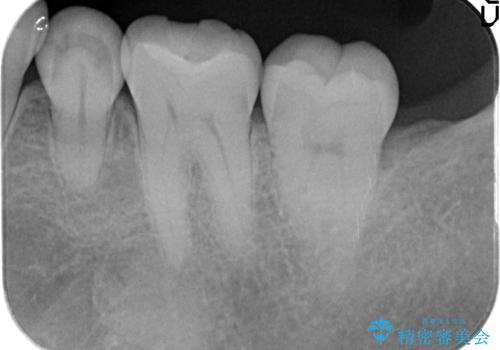

- 左下6番目の歯がしみるので診て欲しいといらっしゃった方の症例です。

古い樹脂及び虫歯を除去後、セラミックインレーによる修復を行いました。